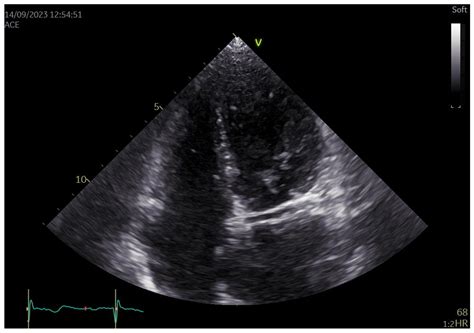

Echocardiogram Visualizes wall motion abnormalities in the area supplied by the LCx.